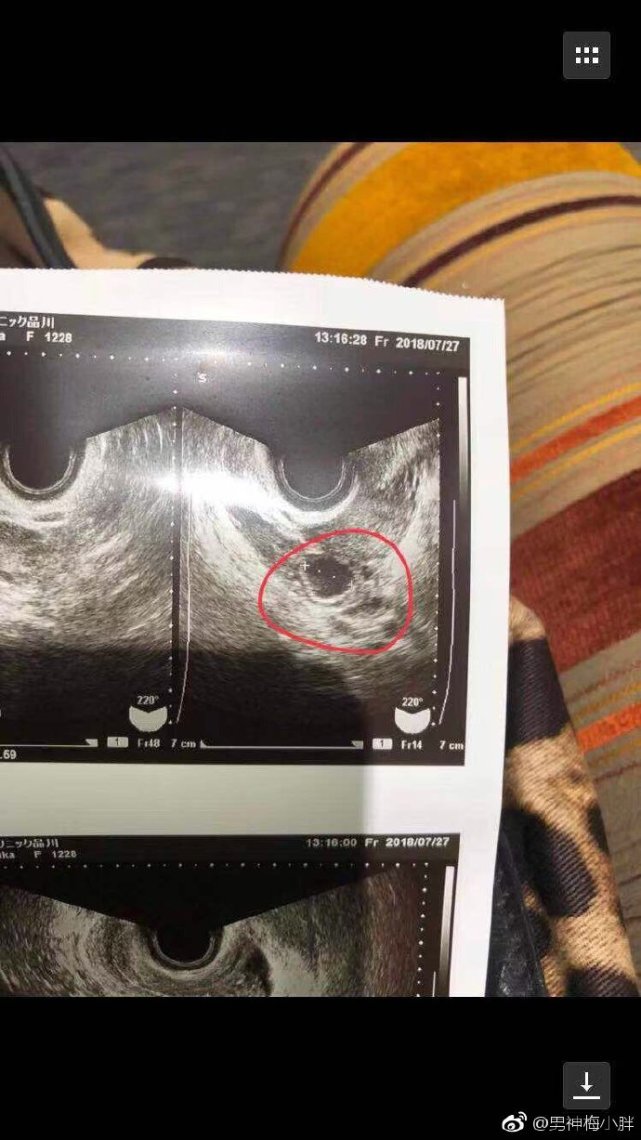

彩超照片

蒋劲夫在不久后突然告诉作者自己女友可能怀孕,女生称自己月经没有按时来,但验孕棒查验结果却是没有怀孕。作者得知蒋劲夫女友长期服用避孕药,怀疑是停用避孕药的反应,但女生坚称自己月事一向正常,肯定自己怀孕。在作者提议蒋劲夫带其去医院检查时,女孩拿出了B超单集化验单,由于作者的妻子正在怀孕中,对比了该女生提供的化验单可以发现女孩并未怀孕。但蒋劲夫选择相信女孩,并考虑结婚。该作者还表示,蒋劲夫与女生在一起的几个月间里花了不少钱,加之女生要求买房以及此次要求的巨额谈金事件,整件事情疑点众多。